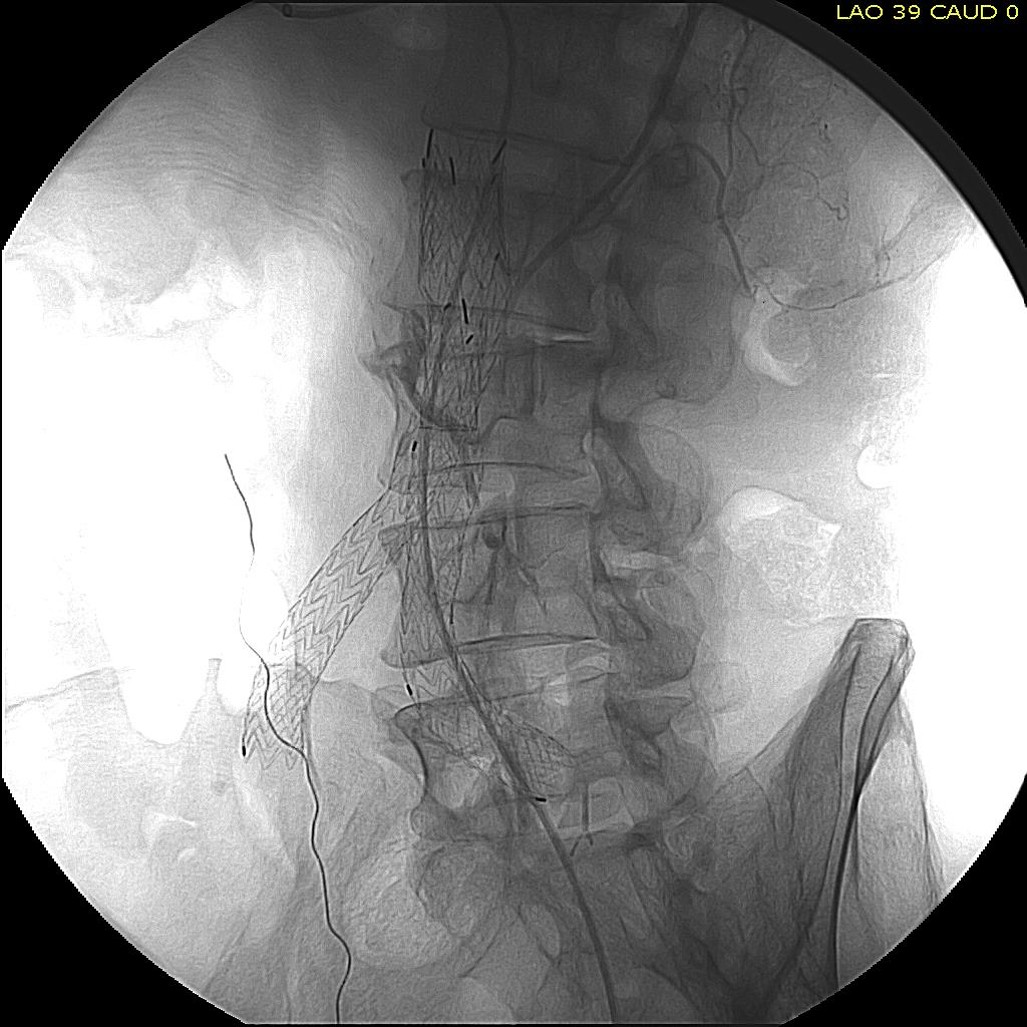

The first step in the access involves getting stable footing in the SMA. Selective access can be performed with a shaped catheter, and once accessed, a Rosen wire is used to track in a curved long sheath. Parking this sheath in the proximal SMA forms the foundation of this machine. The next step is access into the middle colic artery.

The CTA is particularly helpful in identifying the middle colic on the 3DVR projection. Selection of this is straightforward with a an angle catheter which I place a Tuohy Borst connector. This is the second stage of the machine, because further access with 0.35guage wires and catheters could result in spasm. This second sheath access (the Tuohy turns the catheter into a sheath) of the middle colic allows for selective 0.18 gauge catheters and wires to make the final step to the IMA and the AAA.

The embolization with NBCA sealed the IMA and the cavity in the AAA sac. This was checked with intraoperative duplex, done with a transabdominal aortic probe.

The access machine concept is important for planning interventions. Every major branch or turn needs to be crossed by your ultimate access sheath, if you want to avoid having to arduously reaccess those points, and building up a telescoping layer of sheaths is very handy. Every interventional case is done at some distance away from the access point on the skin, and so some though has to be given to how you will build that machine.